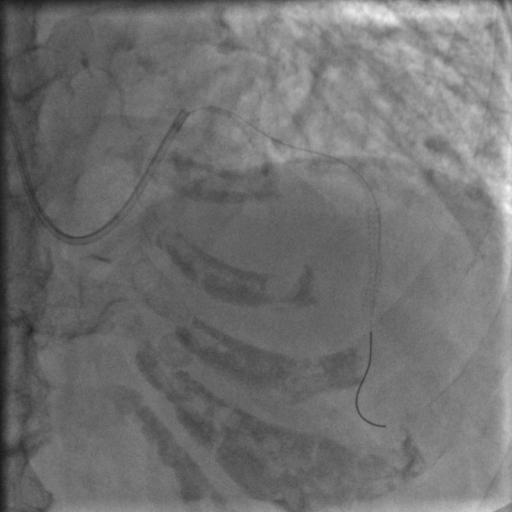

导丝过了之后常规造个影:

图6

没通,这个也很正常,急性冠脉闭塞导丝过了之后血栓还堵着是很经常的事,按常规打点欣维宁,考虑到她86岁,打入8ml欣维宁,造影: